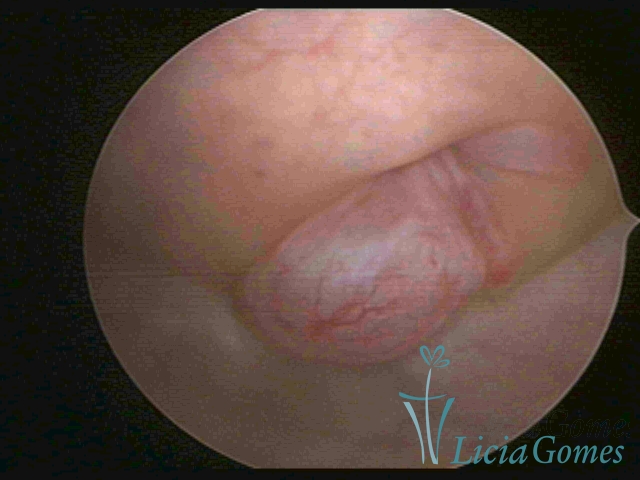

PÓLIPOS ENDOCERVICAIS

São tumores benignos, resultantes da proliferação focal reativa aos processos inflamatórios ou à situações de hiperestrogenismo, e podem ter sésseis (com a base de implantação larga) ou pediculados do epitélio.